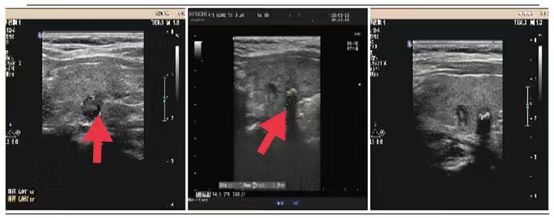

02、**男士,58岁

2023年8月3日在邯郸仁泰东区体检,腹部彩超检查提示:右肾实性占位性病变,大小为3.8*3.3cm(性质待定),建议进一步检查。首次回访2023年8月4日,通知客户去三甲医院进一步检查和治疗。2023年9月3日跟踪回访,客户反馈在邯郸两家三甲医院检查都建议手术治疗,后选择邯郸市中心医院手术,术后病理诊断肾恶性肿瘤。